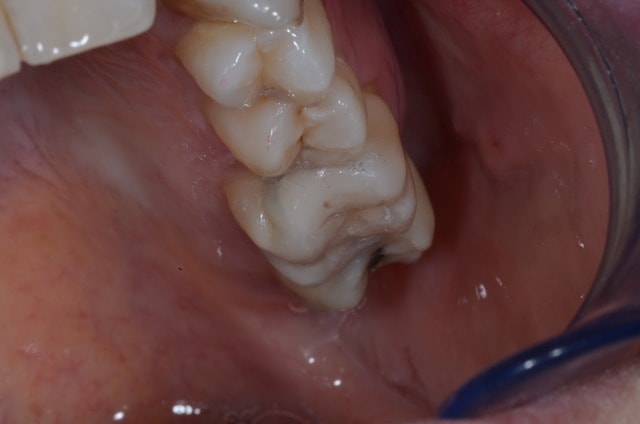

Inlay onlay de l'après-midi ^^ 47

Photo 075 lgka1x - Eugenol

Photo 074 hnkwkc - Eugenol

Photo 078 rn8wwz - Eugenol